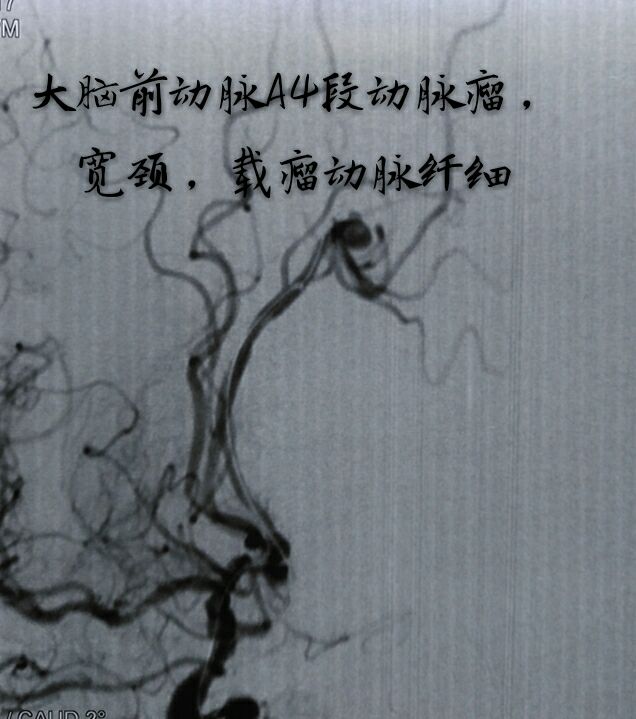

病例十一:大脑前动脉A4段动脉瘤,宽颈,载瘤动脉纤细

支架辅助下动脉瘤致密栓塞,难点:动脉瘤位置远,通路迂曲,使用8F GUIDING置于颈内动脉C2段,内套6F Navien置于床突段完成